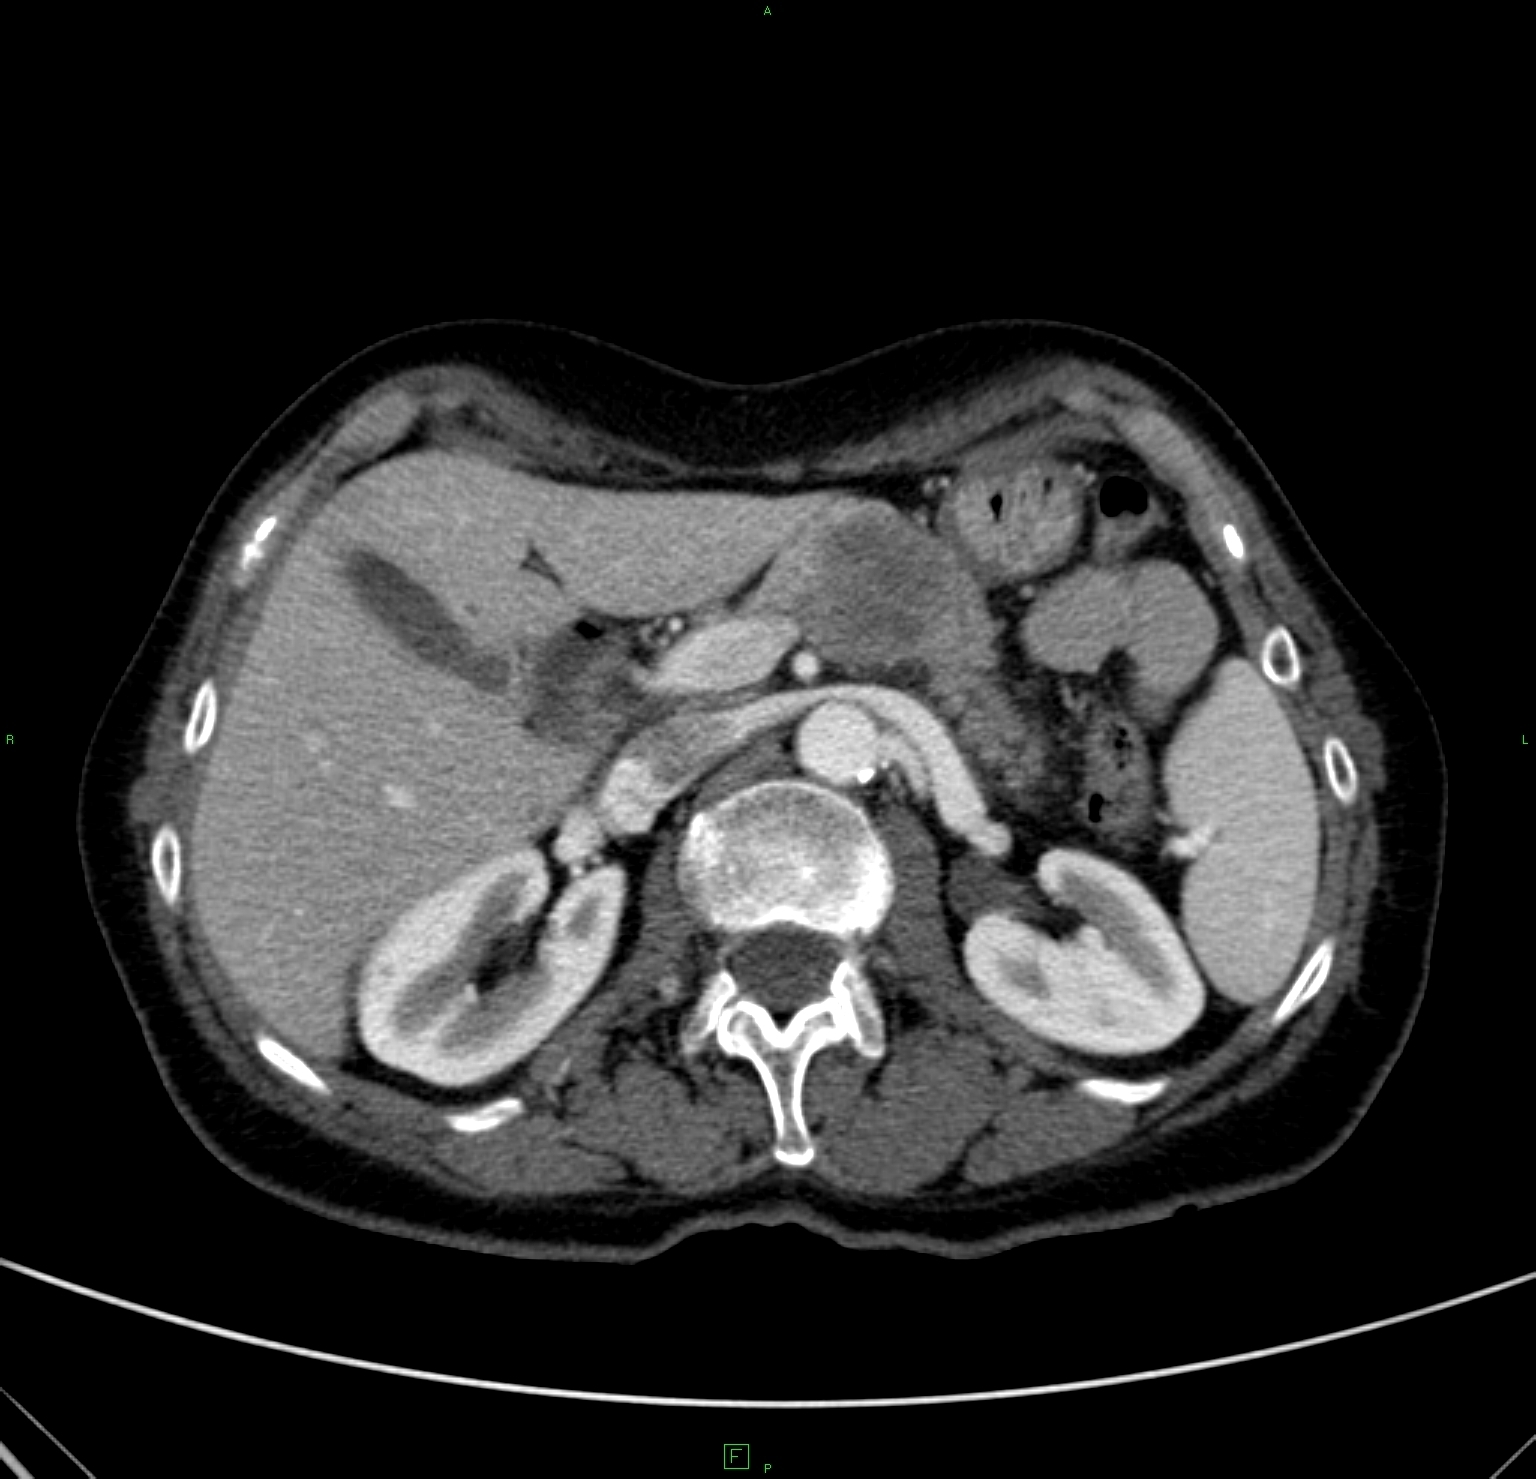

CT classification of the pancreatitis according to Balthazar:

Stage A (0) - normal pancreas

Stage B (1) - focal or diffuse pancreas enlargement (Figure 39)

Stage C (2) - gland structure swelling with peripancreatic inflammatory signs

Stage D (3) - pancreatogeneous fluid content in one localisation (Figure 40)

Stage E (4) - two or more fluid content and/or gas content in the pancreas or in the adjacent area (Figure 41)

Figure 39: Acute pancreatitis, native CT, diffuse early enlargement

Figure 40: Acute pancreatitis, contrast enhanced CT, fluid in front of the body and the tail

Figure 41: Subacute pancreatitis, contrast enhanced CT, coronal reconstruction, extensive formation of pseudocysts in the body-tail region

In case of an acute pancreatitis, the early flare (swelling) of the gland structure and fluid content formation in various extent can be observed, furthermore the determination of extent of the tissue necrosis is crucial.